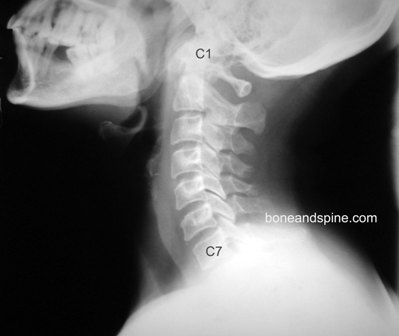

Bad News #3- When he first looked at this picture, he asked me “Have you ever been diagnosed with scoliosis?” No. “Well, you certainly have some going on here.” As you can see, my spine doesn’t exactly resemble a straight spine. It is all sorts of wonky. So you can see why my back has been hurting.